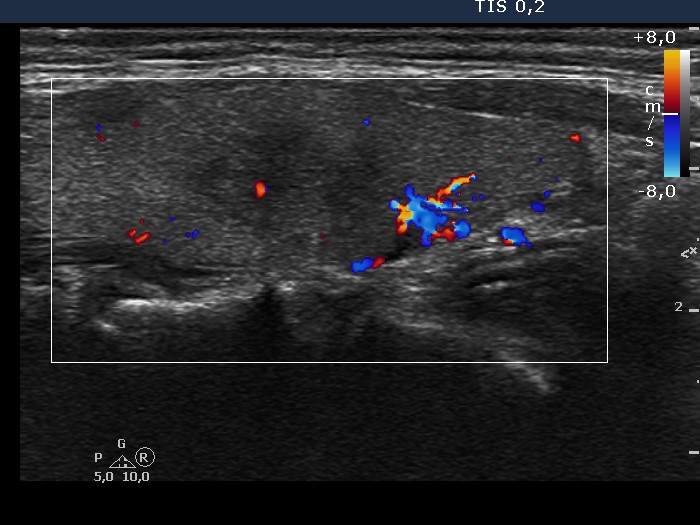

Right lobe, longitudinal view, color Doppler mode.